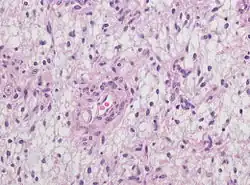

For further confirmation, the clinicians require biopsy and immunohistochemical staining of the resected tumor after surgery. The infiltrative AG cells display positive results for several immunostainings, especially the glial fibrillary acidic protein (GFAP) and epithelial membrane antigen (EMA).[1] Clinicians also observe a specific dot-like pattern from the stained EMA photomicrograph.[3] Other specific AG immunohistochemical tests include Ki-67 proliferative marker, neurospecific nucleoprotein (NeuN), protein 53, synaptophysin (Syn), oligodendrocyte transcription factor-2 (Olig-2) and creatine kinase (CK).[3] In the 2016 WHO classification of CNS tumors, AG is characterised as GFAP-positive, NeuN-positive and low Ki-67 proliferative rate with a perivascular growth pattern.[13]